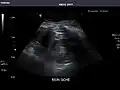

Abdominal ultrasonography (also called abdominal ultrasound imaging or abdominal sonography) is a form of medical ultrasonography (medical application of ultrasound technology) to visualise abdominal anatomical structures. It uses transmission and reflection of ultrasound waves to visualise internal organs through the abdominal wall (with the help of gel, which helps transmission of the sound waves). For this reason, the procedure is also called a transabdominal ultrasound, in contrast to endoscopic ultrasound, the latter combining ultrasound with endoscopy through visualize internal structures from within hollow organs.

Ultrasonography of the kidneys is essential in the diagnosis and management of kidney-related diseases. The kidneys are easily examined, and most pathological changes in the kidneys are distinguishable with ultrasound.[7]